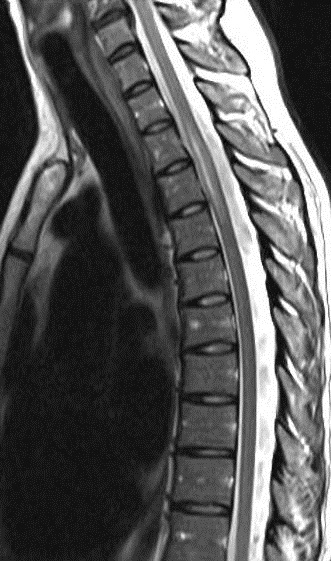

A MRI scan of brain and spine showed increased T2 signal and expansion of the cord in some areas of the spinal cord at the levels of C2–C5, and C7 to T12. The patient was given methylprednisolone 1 gram intravenous for a period of 5 days and oral steroids for 4 weeks. Thyroid function tests were reported to be normal (Table 3 [Tab. 3]). The patient showed marginal improvement in vision and reduction of sensory abnormalities by about 50% over a period of 6 weeks. In April 2015, the patient was admitted with cough associated with mucopurulent expectoration, shortness of breath, paraesthesias and diminished vision. The patient showed minimal improvement in sensory symptoms or vision. In May 2015, the patient was admitted with progression of bilateral lower limb weakness, bilateral upper limb weakness (distal > proximal) and a band-like sensation around the chest, syncope, vomiting and hiccups. Clinical examination revealed normal higher mental functions with diminished vision to finger counting in the right eye. Other cranial nerves were normal.

Immunological tests for ANA titer were 1:320, tests for anti-ENA, anti-dsDNA, anti-cardiolipin, anti-β2GPI, lupus cells, antibodies to GAD65, IA-2, insulin and cryoglobulins were negative. MRI brain and whole spine revealed 1) hyperintensity in cervical cord C5 to C7 level (Figure 1 [Fig. 1], Figure 2 [Fig. 2], Figure 3 [Fig. 3]); 2) hyperintensity in the thoracic cord till T12 level (Figure 4 [Fig. 4], Figure 5 [Fig. 5], Figure 6 [Fig. 6]); 3) hyperintensity in the right optic nerve head (Figure 7 [Fig. 7]). The clinical features and investigations (NMO IgG was positive) fit into the criteria of neuromyelitis optica. The thyroid profile was suggestive of hypothyroidism (Table 3 [Tab. 3]). Laboratory studies confirmed the presence of antithyroid antibodies (Table 4 [Tab. 4]). Fine needle aspiration of the thyroid showed lymphocytic infiltration of the thyroid gland (Figure 8 [Fig. 8], Figure 9 [Fig. 9]). The patient was treated with prednisolone 1 g/day for 5 days and azathioprine (2.5–3 mg/kg/daily). The patient showed improvement in motor symptoms and sensory symptoms approximately by 60% after a period of 2 months of treatment. Patient was started on thyroxine 50 μg and later dosage was increased to 100 μg.